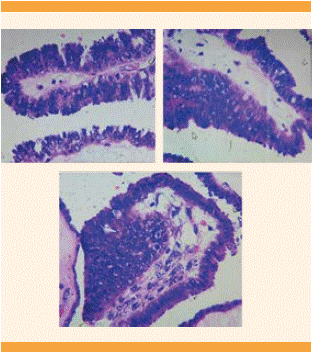

Figura 4 Microfotografía de TLO, con implantes en la cápsula sin datos de invasión por tumor seroso papilar.

Figura 5 Microfotografía de TLO seroso con formaciones micropapilares en forma de “medusa”, sin infiltración al estroma ovárico.